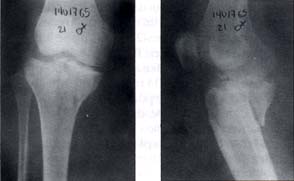

En 14 casos (88%) el tratamiento fue quirúrgico, el abordaje fue posterior entre las dos cabezas del gastrocnemio y en dos pacientes (12%) se realizó un doble abordaje anterior y posterior. La osteosíntesis se realizó con tornillos de esponjosa en cuatro pacientes (25%) como se ilustra en la figura 2 y con placa en T en 10 pacientes (62%) como se ilustra en la figura 3.

Fig. 3. Paciente de 21 años de sexo femenino con fractura del platillo tibial posteromedial y osteosíntesis con placa y tornillos.